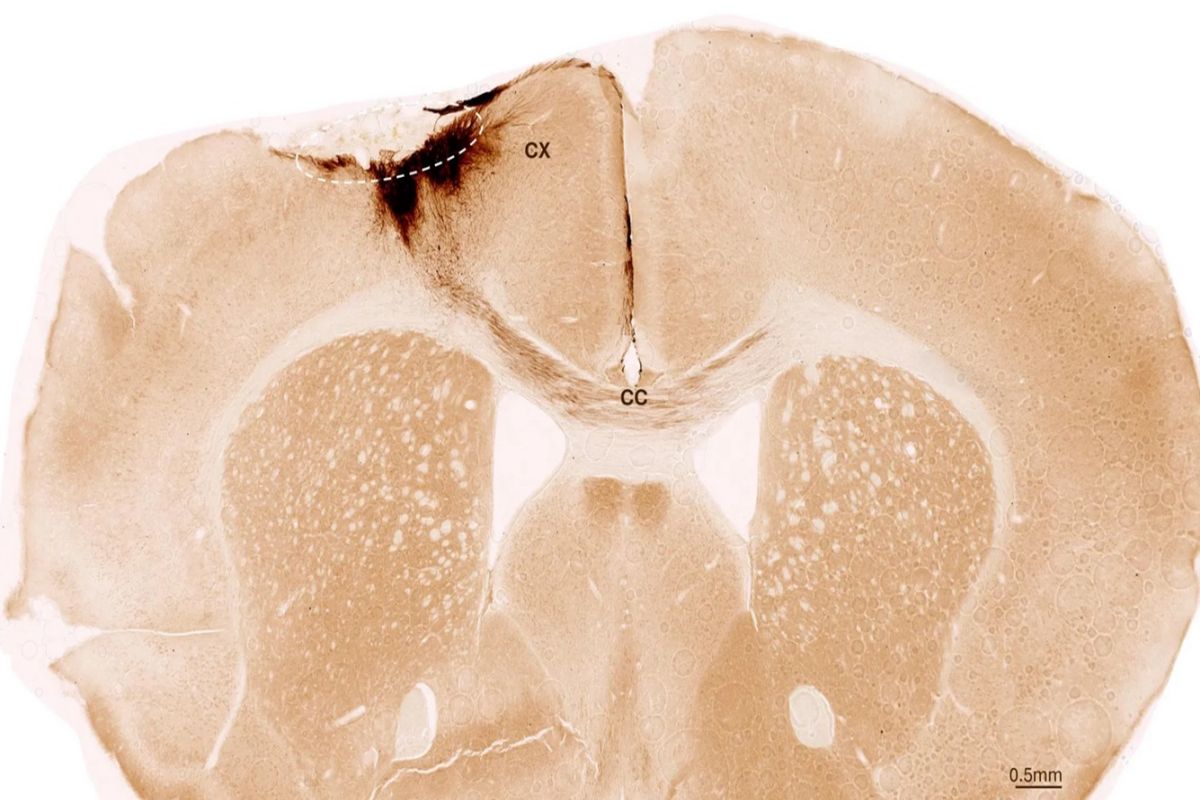

Ερευνητές του Πανεπιστημίου της Ζυρίχης έδειξαν, μέσα από πειράματα σε ποντίκια, ότι η μεταμόσχευση βλαστοκυττάρων μπορεί να αναστρέψει τις βλάβες του εγκεφαλικού επεισοδίου αναγεννώντας τους κατεστραμμένους νευρώνες, αποκαθιστώντας την κινητικότητα, ακόμη και «επιδιορθώνοντας» τα αιμοφόρα αγγεία που έχουν πληγεί από το επεισόδιο.